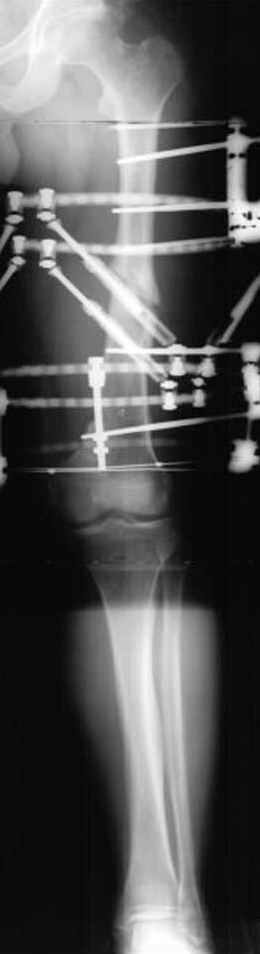

пластическая модель; и коррекция бедра аппаратом Илизарова.

Имею другие снимки тоже, получится как отчет о моей работе.

С уважением Джолдас